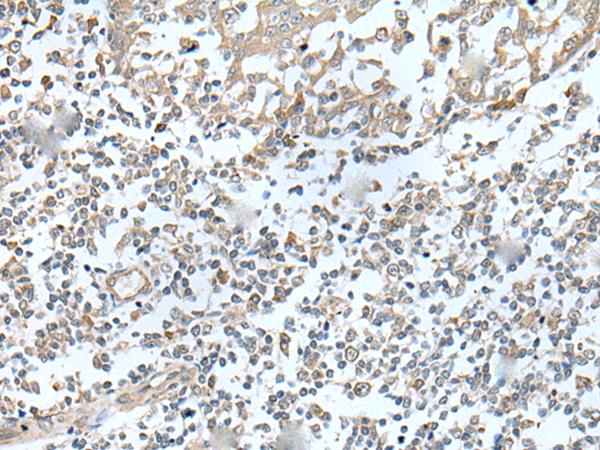

ELISA, IHC |

IHC positive control: |

Human brain and human lung cancer |

IHC Recommend dilution: |

50-350 |